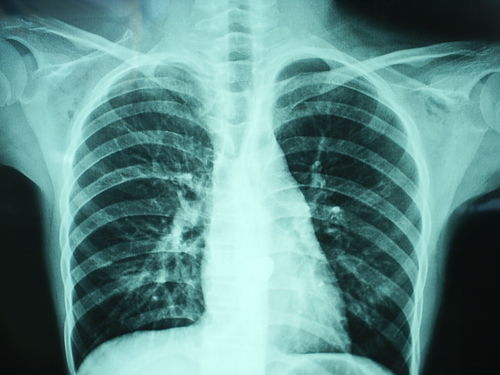

胸透可以看到胸部的軟組織、骨骼(包括胸椎)、縱隔(心臟、大血管、氣管、食管等)、氣管和支氣、胸膜、肺組織等??梢栽\斷肺和氣管的先天性疾病,如發(fā)育異常、肺部的各種炎癥、急慢性支氣管炎、比較明顯的支氣管擴(kuò)張癥、肺氣腫或肺水腫、各型肺結(jié)核、肺腫瘤、胸腔積液、氣胸、縱隔腫瘤、心臟形態(tài)異常等

健康查體最常做的是胸部的X線檢查,最基本的就是胸透。 胸透可以看到胸部的軟組織、骨骼(包括胸椎)、縱隔(心臟、大血管、氣管、食管等)、氣管和支氣、胸膜、肺組織等。

可以診斷肺和氣管的先天性疾病,如發(fā)育異常、肺部的各種炎癥、急慢性支氣管炎、比較明顯的支氣管擴(kuò)張癥、肺氣腫或肺水腫、各型肺結(jié)核、肺腫瘤、胸腔積液、氣胸、縱隔腫瘤、心臟形態(tài)異常等。